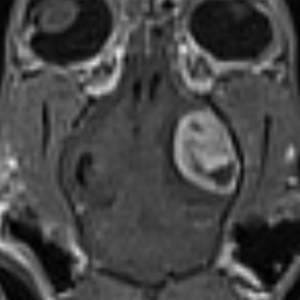

Gehirntumor (Meningiom) bei einer Katze I © Kleintierklinik der LMU

Desweiteren werden Tumorentfernung im Bereich des Gehirns (zB Meningiom Katze) oder Tumorbiopsie/- verkleinerung (sofern nicht resizierbar) durchgeführt, um nach einer histologischen Diagnosestellung adäquate weitere Therapieempfehlungen (meist Bestrahlung) zu geben.